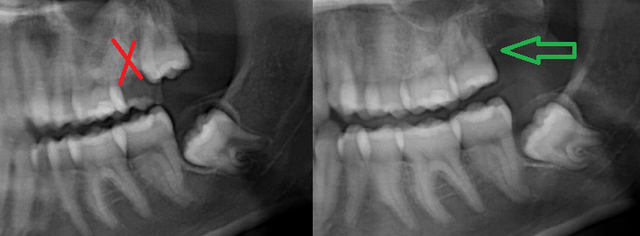

33.74 + radio

Dsc 0045 wbiuns - Eugenol

Dsc 0046 dz7bl1 - Eugenol

cyril écrivait:

> 33.74 + radio

uep mais t as gagné du matériau de comblement pour plus tard en pétant la tubérosité..